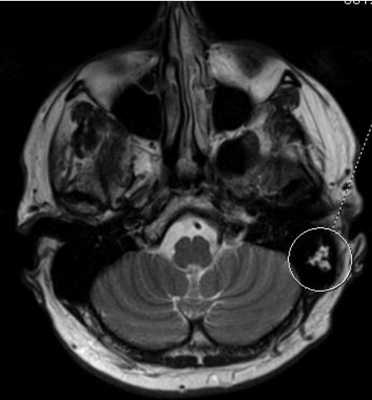

МРТ головного мозга. В аксиальной плоскости отмечается повышение интенсивности МР-сигнала в области ячеек сосцевидного отростка левой височной кости (круг) вследствие ранее перенесенных воспалительных изменений.

Признаки арахноидальной кисты (указана стрелками) на томограммах ММУ